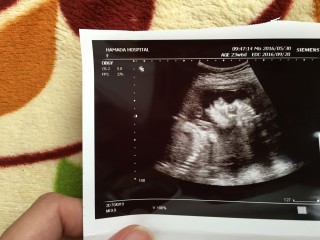

写真:23w6d:せとむさん:670g

670gの推定女の子です。参考になればと投稿しました♪